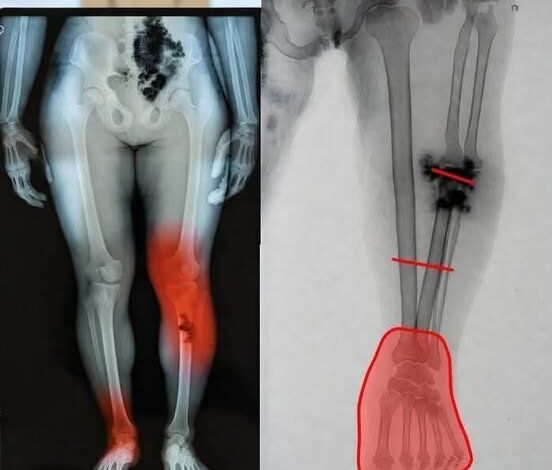

The images in question typically depict lower leg and foot trauma, showing shattered bone structures or mysterious “growths.” While the visuals are undeniably distressing, radiologists and orthopedic specialists have been quick to intervene. Upon closer inspection, these X-rays do not show the systemic cellular response one would expect from a pharmaceutical side effect. Instead, they display the hallmark signatures of localized trauma, advanced untreated infections (such as osteomyelitis), or severe vascular compromise—conditions that existed long before the advent of mRNA technology and are entirely unrelated to the mechanics of vaccination.

To the untrained eye, a dark spot or a jagged line on an X-ray is a sign of catastrophe. To a specialist, it tells a specific story. Dr. Elena Rodriguez, a senior radiologist, notes that the images being circulated as “vaccine damage” are actually clinical examples of late-stage diabetic complications or high-impact fractures. “Bones do not simply disintegrate or shift because of an immune response,” Rodriguez explains. “The pathologies shown in these viral posts are the results of years of underlying disease or sudden, violent physical force.”